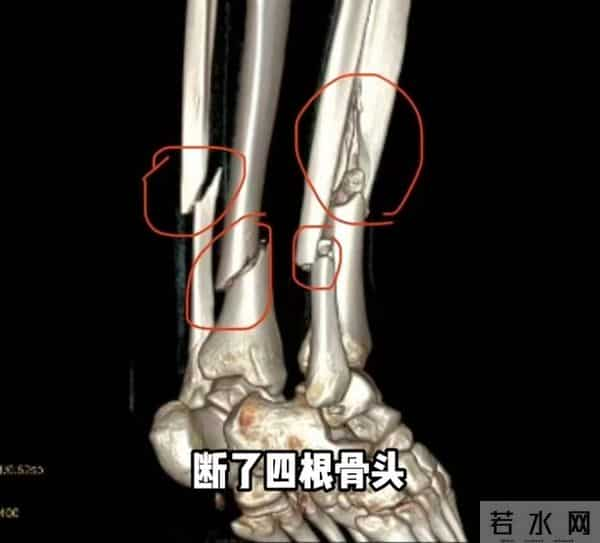

据她2月27日发布的动态,她在新疆滑雪时摔倒,断了4根骨头,右腿胫骨粉碎性骨折,处理伤口的时候,她痛苦喊叫声响彻诊室。

据她描述,轻微的活动都能感受到碎骨扎进肉里,不敢想象有多疼。

千一称在新疆接受手术,左腿2块钢板16颗钉子,右腿2条髓内钉和6颗固定钉子,缝了45针。